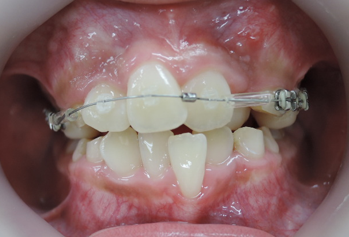

よく診る、難しい症例(奥歯の隙間)

歯列不正

歯を抜かないと治療出来ないと言われた方に。(歯並びが悪い)